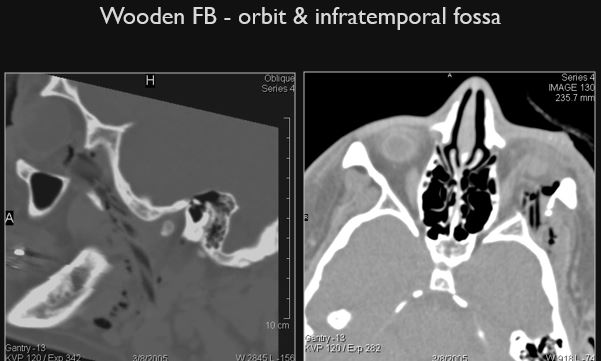

There is an air (low density) pattern, either a tract or “geometrically shaped”, suggestive of a penetrating injury in areas of soft tissue swelling or elsewhere. [Yes/No]

There is one or more “geometrically shaped” low density structures suggestive of a non radiodense foreign body presence. [Yes/No]